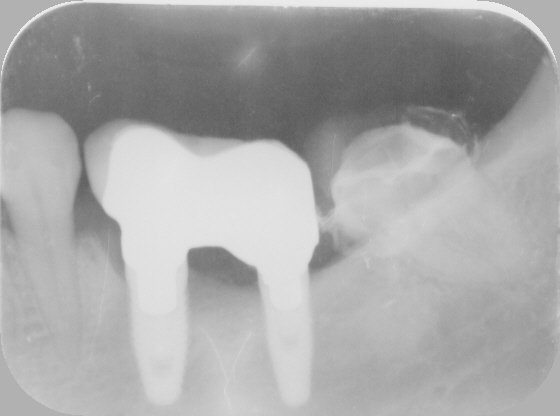

Paciente con implante en 26 acude para cambiar la corona. Es un hexágono externo pero la distancia entre lados del hexágono es entre 3.2 y 3.5, métrica 1.8, creo que [...]